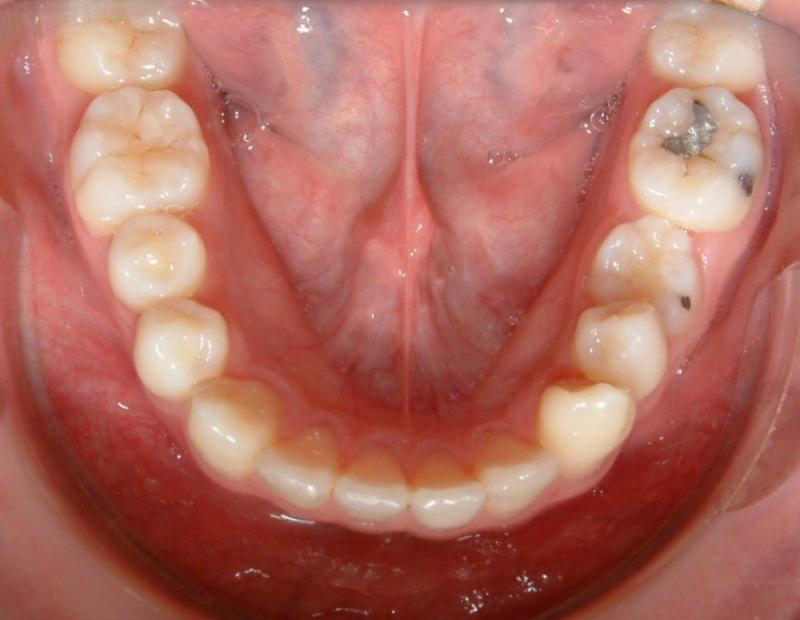

Fig. 1. The lower midline is shifted to the patient's left.

© Copyright 2007-2014, Vu Orthodontics. All rights reserved.